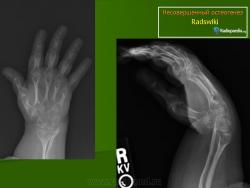

Рентгенологические изменения зависят от тяжести патологического процесса. Основным признаком является распространенный остеопороз всего скелета. Окружающие срастающийся перелом периостальные мозоли иногда достигают огромных размеров, симулируя опухоль (псевдосаркома). Отмечаются резкое истончение кортикального слоя, уменьшение диаметра кости. Характерна платиспондилия различной степени; позвонки приобретают двояковогнутую форму. Черепные швы расширены, с большим количеством непостоянных так называемых вормиевых косточек.

Рентгенологически. Выражен остеопороз костей, истончение кортикального слоя, следы множественных переломов и избыточного мозолеобразования, укорочение костей, сколиоз или кифосколиоз.